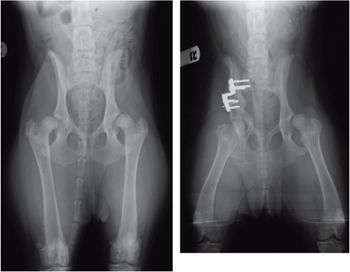

Although it is expensive,TPO surgery can spare the dysplastic dog a lifetime limited by pain.